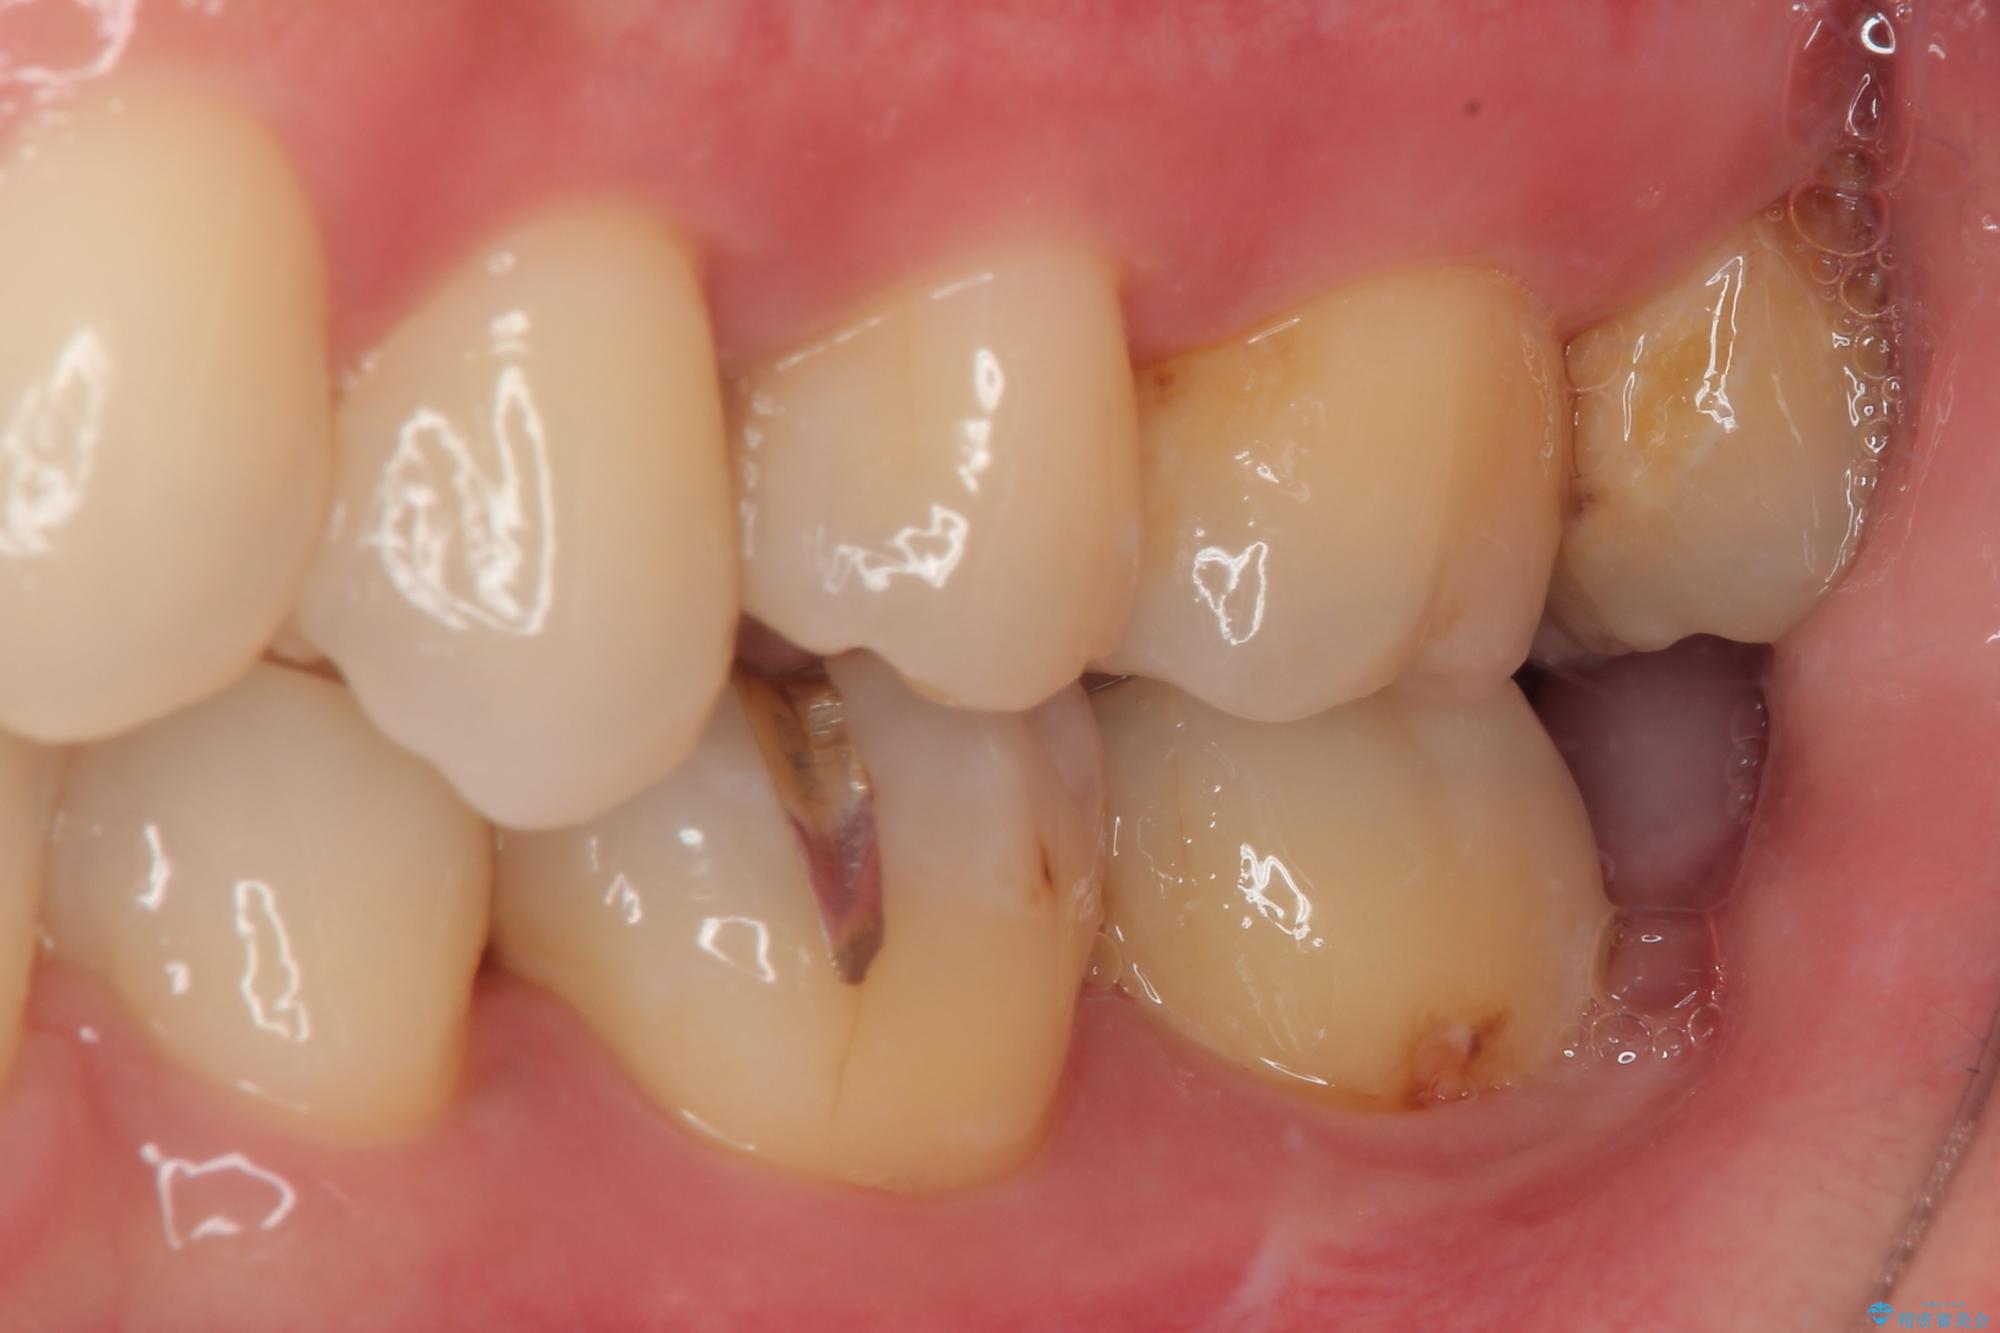

矯正治療により処置が可能な位置に歯が移動したため、オールセラミッククラウンにて補綴治療を行うこととしました。

歯列が移動したとはいえ、左右ともに後方傾斜しており、むし歯の除去、形成(形を整える)、型取りの全てが非常に困難な処置となりました。

セラミッククラウンの適合はレントゲン写真からも分かる通り、境界がぴったりと合った、高適合のものとなりました。